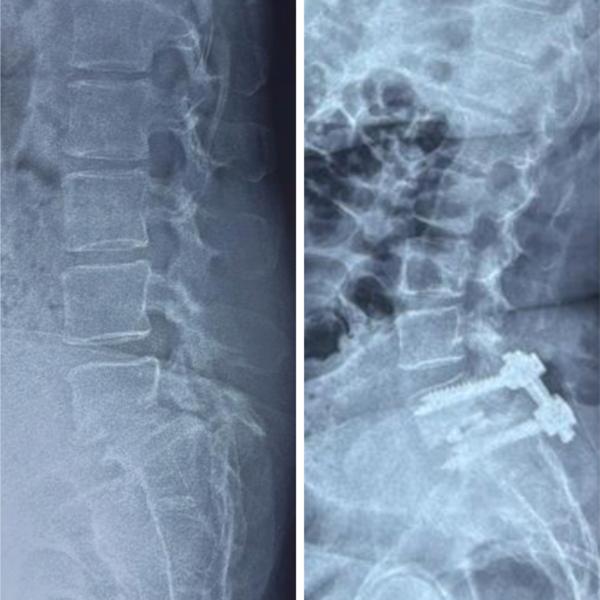

TLIF surgery for L5S1 Lumbar Spondylolisthesis #s...

View Details